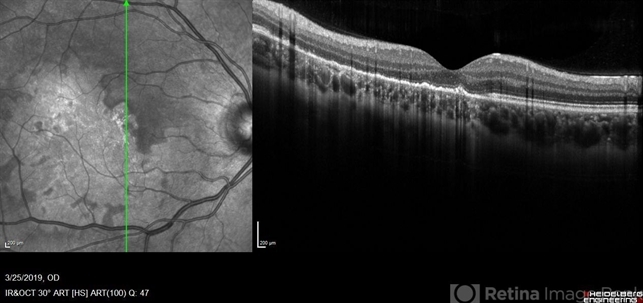

- macula serpiginous choroidopathy, optical coherence tomography (OCT), Heidelburg Spectralis, macula lesion

Optical coherence tomography system

Heidelberg Spectralis - Description

- Heidelberg single vertical scan image of 20-year-old female presenting with serpiginous choroidal atrophy. Patient was unaware of vision loss OD, until accidentally covering OS and noticing the change. Acuity of 20/200 OD and 20/15 OS at time of imaging.